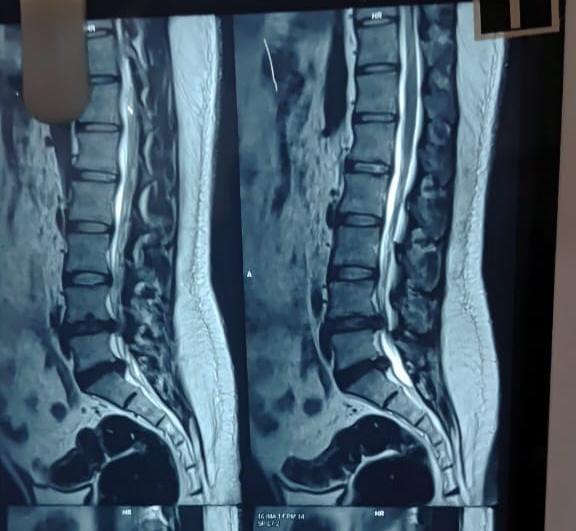

READ MORESunshine Ortho Pain And Superspeciality Hospital is the Best Orthopedic Hospital in Wakad, Hinjewadi, PCMC and Pune. We are specialized in Orthopedic Surgeries, Robotic Joint Replacement Surgery, Hip and Knee Replacement Surgery, Complex Trauma And Pelvi Acetabular Surgery, Spine Surgery, Sports Medicine And Arthroscopy, Regenerative Therapy/Prolotherapy, Physiotherapy and Rahabilitation Center, Shoulder Surgery, Knee Surgeries, Foot And Ankle Treatment, Fracture Treatment in Wakad, Hinjewadi, PCMc and Pune.

Dr Pravin Deokate is a highly experienced Orthopedic and Joint Replacement Surgeon with 25 years of expertise, serving patients in Wakad, Hinjewadi, PCMC, and Pune. He holds M.B.B.S, M.S (Ortho), M.Ch (Ortho), ITLS (USA), and a Fellowship in Pain Management, specializing in joint replacements, trauma care, and pain management. As a senior surgeon at Sunshine Ortho Pain Superspeciality Hospital, Wakad, he provides advanced, minimally invasive treatments for hip, knee, and complex orthopedic conditions. His patient-focused approach ensures faster recovery and long-term relief. Visit Dr Pravin Deokate for expert orthopedic care.